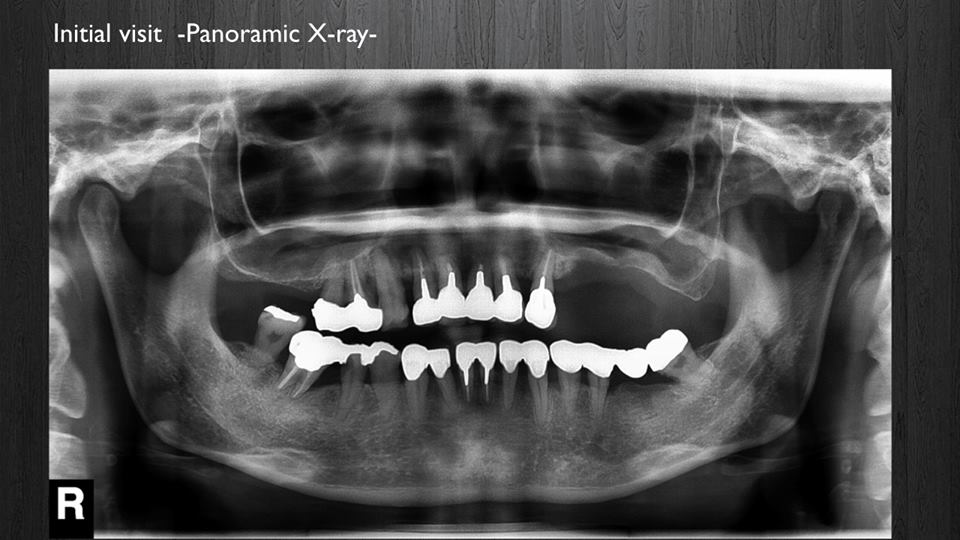

インプラント症例(全顎)

< 症例1 >

- 治療期間:24ヶ月

- 治療回数:126回

- 治療歯数:28歯

- 費用:全顎矯正治療80万円 インプラント治療:155万円 上部セラミック:160万円

- リスク:メンテナンスを怠ると、インプラント周囲炎になる可能性があります。

- インプラント手術には合併症が伴う場合があります。

- 治療期間は治癒の状態により前後する場合があります。